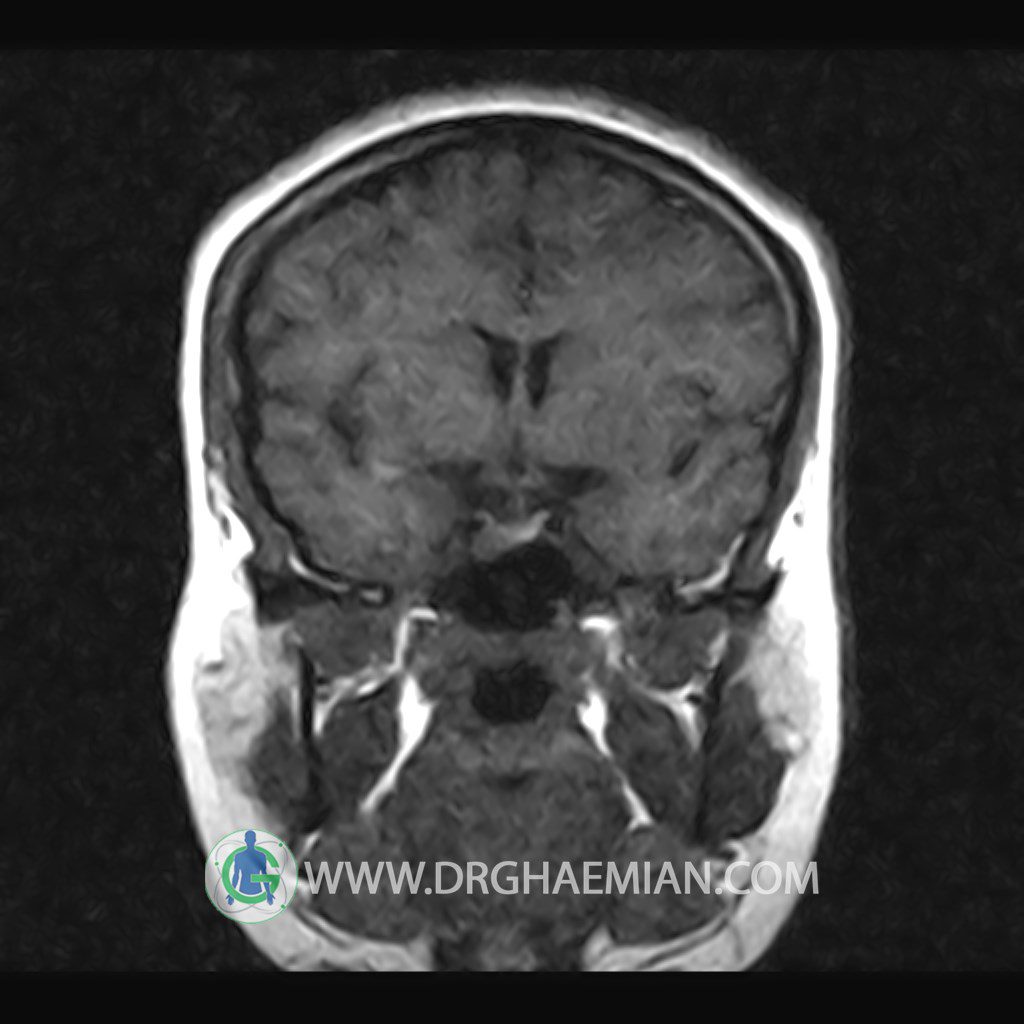

ام آر آی هیپوفیز یک روش تصویر برداری است که از غده هیپوفیز (غده ایی کوچک در مغز که هرومون ها و دیگر غدد بدن را کنترل می کند) و ناحیه های پیرامونش در مغز تصاویری ایجاد می کند. در این کیس سلای نسبتا خالی در ناحیه هیپوفیز بیمار مشاهده می شود.

HYPOPHYSIS MRI

(with and without contrast)

Technique: Axial , coronal T1 , Axial , coronal , sagittal T2 , Axial, coronal T1 post Gd & 64 dynamic thin coronal slices.

The pituitary tissue shows normal , position, shape , size and homogeneous signal intensity both before and after contrast administration .

Anterior and posterior pituitary gland were normal .

It contains no circumscribed hypointense or hyperintense areas .

The infundibulum is centered and of normal size .

The optic chiasm and suprasellar spaces appear normal .

The cavernous sinus and imaged portions of the internal carotid artery and carotid siphon are unremarkable .

Evaluable portions of the neurocranium show no abnormalities .

The sphenoid sinus is clear and pneumatized .

Imaging of the hypothalamus after contrast medium administration was normal.

– Extension of suprasella cistern to sella with thin pituitary gland in floor of sella ( partial empty sella )

is seen